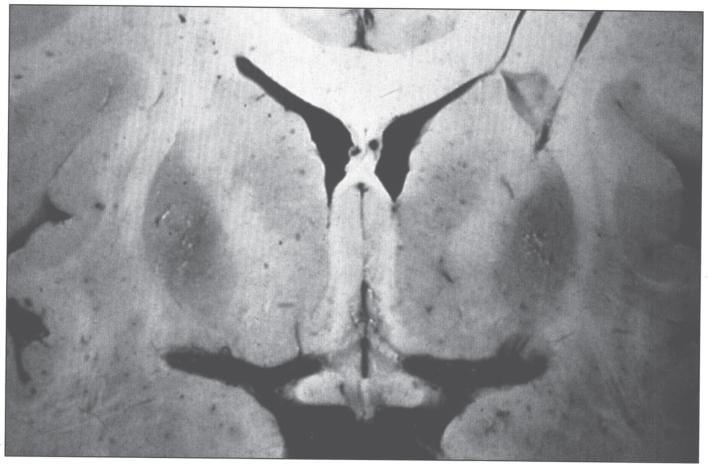

Trace elements are chemical elements needed in minute amounts for normal physiology. Some of the physiologically relevant trace elements include iodine, copper, iron, manganese, zinc, selenium, cobalt and molybdenum. Of these, some are metals, and in particular, transition metals. The different electron shells of an atom carry different energy levels, with those closest to the nucleus being lowest in energy. The number of electrons in the outermost shell determines the reactivity of such an atom. The electron shells are divided in sub-shells, and in particular the third shell has s, p and d sub-shells. Transition metals are strictly defined as elements whose atom has an incomplete d sub-shell. This incomplete d sub-shell makes them prone to chemical reactions, particularly redox reactions. Transition metals of biologic importance include copper, iron, manganese, cobalt and molybdenum. Zinc is not a transition metal, since it has a complete d sub-shell. Selenium, on the other hand, is strictly speaking a nonmetal, although given its chemical properties between those of metals and nonmetals, it is sometimes considered a metalloid. In this review, we summarize the current knowledge on the inborn errors of metal and metalloid metabolism.

微量元素是正常生理功能所需的微量化学元素。一些与生理相关的微量元素包括碘、铜、铁、锰、锌、硒、钴和钼。其中,有些是金属,特别是过渡金属。原子的不同电子壳层具有不同的能级,最靠近原子核的电子壳层能量最低。最外层电子的数量决定了该原子的反应活性。电子壳层又分为子壳层,特别是第三壳层有s、p和d子壳层。过渡金属被严格定义为原子具有不完全d子壳层的元素。这种不完全的d子壳层使它们易于发生化学反应,特别是氧化还原反应。具有生物学重要性的过渡金属包括铜、铁、锰、钴和钼。锌不是过渡金属,因为它有一个完整的d子壳层。另一方面,严格来说硒是一种非金属,尽管鉴于其化学性质介于金属和非金属之间,它有时被视为类金属。在本综述中,我们总结了目前关于金属和类金属代谢先天性缺陷的知识。